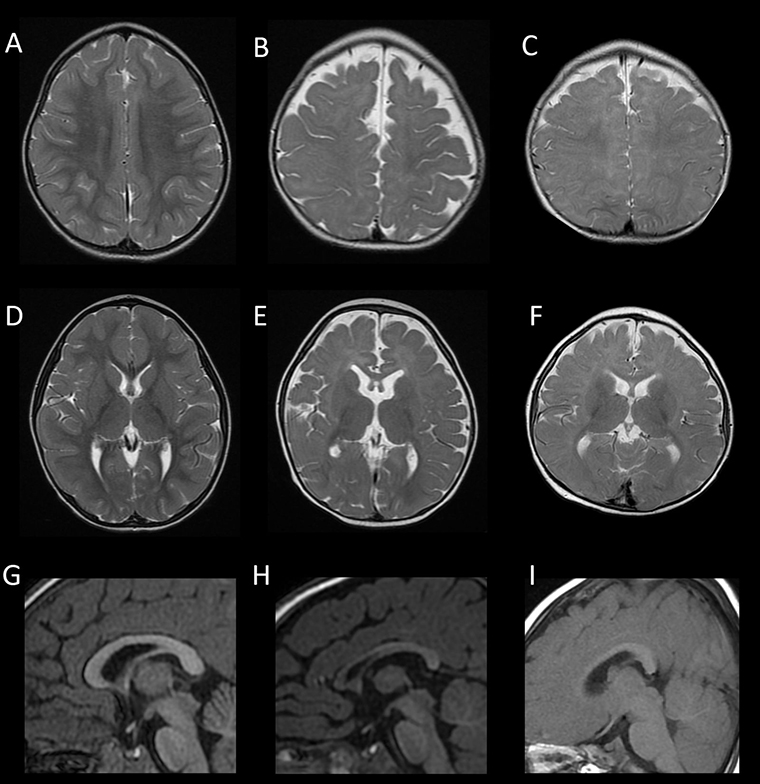

陽明交大腦科學研究所蔡金吾特聘教授與台大兒童醫院院長李旺祚醫師,分析來自歐洲、北美、日本與台灣等國共14名FOXG1症候群患者的臨床症狀與腦部影像資料,建立一項結合實驗室功能檢測的創新流程,包含蛋白表現分析、基因調控測試與小鼠胚胎細胞遷移實驗3種方式,成功預測超過9成病患腦部異常的嚴重程度。這項突破刊登在國際權威期刊《Molecular Psychiatry》 (分子精神醫學)。

# 首圖來源/國立陽明交大腦科學研究所提供